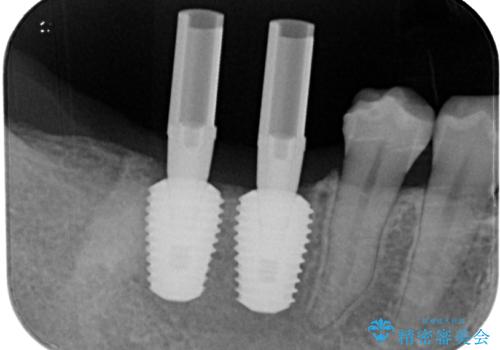

スペースが整った段階で、右下の第一大臼歯と第二大臼歯にインプラントを埋入。